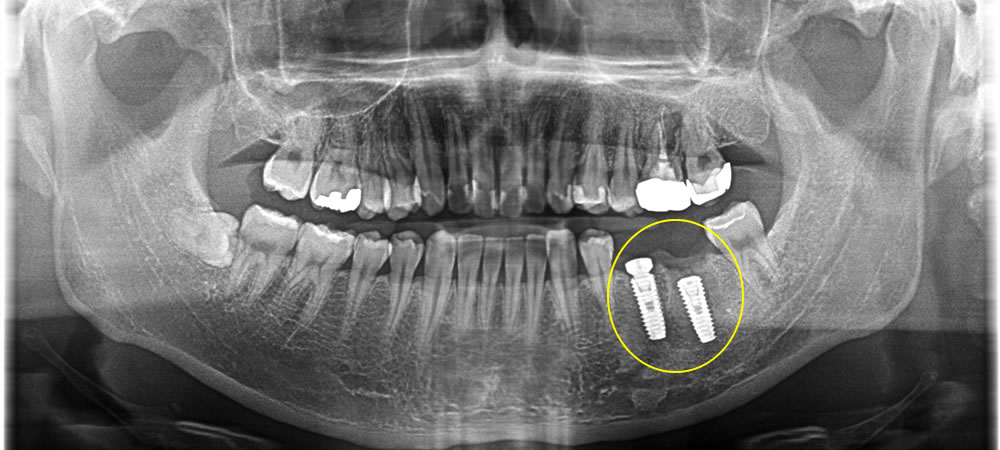

放置してしまった期間が長かったせいで手前の歯にも膿が溜まってしまっていたため、2本抜歯し、インプラントを埋入しました。膿が大きく、骨の欠損範囲も大きかったため、骨を増やすための骨造成も合わせて行いました。

上部構造の装着・治療完了

製作した上部構造を装着し、最終的な咬み合わせを調整して治療完了となりました。骨造成を行ったため、インプラントも骨としっかりと定着し、硬いものも問題なく噛むことができるようになりました。